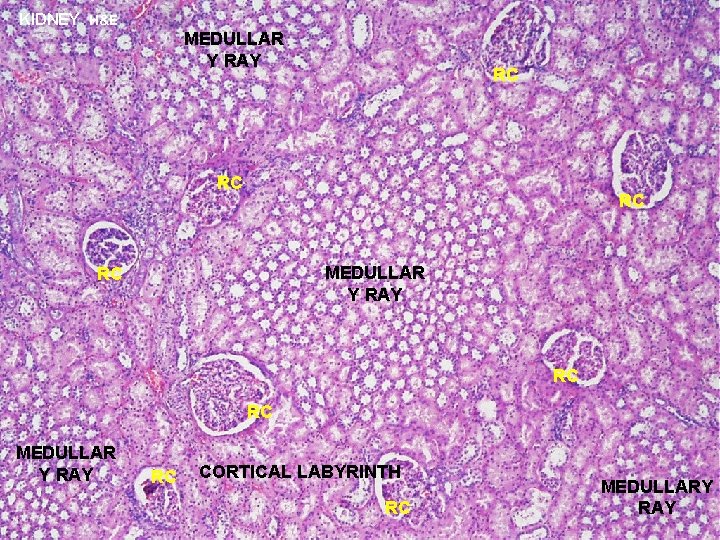

URINARY SYSTEM P KIDNEY (ORGANIZATION) CORTEX P P P - region immediately beneath renal capsule - composed of two distinct regions: P (1) CORTICAL LABYRINTH (2) MEDULLARY RAY P P MEDULL A - located immediately beneath renal cortex - consists of triangular blocks of tissue called the PYRAMIDS - RENAL COLUMNS are strands of cortical tissue that extend down between adjacent pyramids RC

URINARY SYSTEM Cortical Labyrinth with interdigitating Medullary Rays KIDNEY (ORGANIZATION) P RENAL LOBE - a single pyramid with its associated overlying cortex P P P RENAL LOBULE - defined within cortex and involves a single medullary ray (central axis of lobule) with adjacent cortical labyrinth - defined as a functional unit that consists of a collecting duct and all the nephrons that it drains P P P

URINARY SYSTEM THE NEPHRON & COLLECTING DUCTS CORTEX: CORTICAL LABYRINTH 1 - RENAL CORPUSCLES 2 - PROXIMAL CONVOLUTED TUBULES 3 - DISTAL CONVOLUTED TUBULES MEDULLARY RAY 1 - STRAIGHT PORTIONS OF PROXIMAL TUBULE (THICK DESCENDING) 2 - STRAIGHT PORTIONS OF DISTAL TUBULE (THICK ASCENDING) 3 - COLLECTING DUCTS